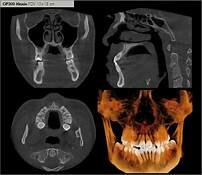

• tomografia cone-beam

tomografia cone-beam

la cual permite ver bien un volumen completo en una sola rotación en su sistema